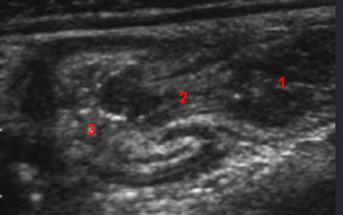

| |

1 - Anse ileale

2 - Valvule

3 - Coecum |

Valvule ileo-coecale :

Image radiologique normale |